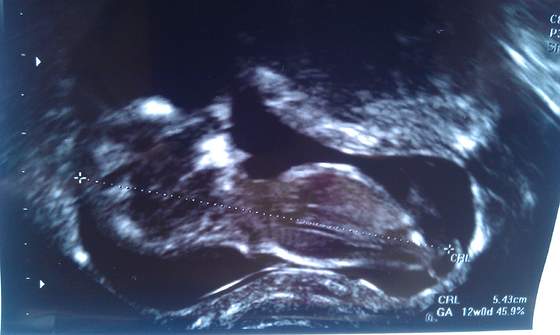

Właśnie wróciliśmy z wizyty. Dzidziuś ma już 5cm, przezierność i nosek ok. Wierzgał podczas badania i wypinał się pupcią do pani doktor.

Jedynie serduszko mu szybko bije :-( FHR 179 i z tego powodu powinnam zrobić test Pappa (szalenie drogi) ale to da nam wiadomość o zdrowiu dziecka

tak, w prywatnej przychodni. Na ekranie dzidziuś prezentował się jeszcze lepiej, ale zdjęcia są takie żeby dr mogła wykonać odpowiednie pomiary